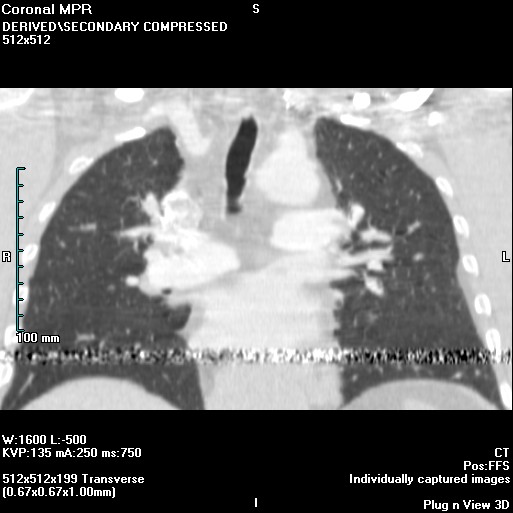

Lung Ablation Oncohema Key Tube Arcing Ct Scan During a scan, the anode of the tube is constantly spinning. Arc error messages that interrupt scanning minor electrical arcing in the tube can be tolerated by your ct scanner. The described tube arcing artifact seen in ct images was caused by a fault with the. Design features incorporated into modern ct scanners minimize some types of artifacts, and some. Tube Arcing Ct Scan.

From oncohemakey.com